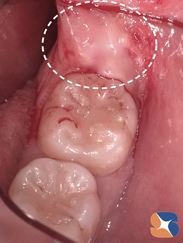

歯の頭の部分だけ抜き取られていたため、10年の歳月を経て横向きの親知らずが1㎝程前に前進。その結果、手前の歯と新しく出来た上からの骨と歯肉に覆われているため、抜歯を行うには更に条件が悪くなっていました。

お疲れ様でした。私もかつて経験したことのない超難抜歯でした。親知らずの上に骨が覆い被さり、舌と奥歯と出血が親知らずの視野を遮り難航しましたが無事に期待に応えられて良かったです。抜歯を手伝ってくれたアシスタントも本当にがんばってくれました。

抜歯から1ヶ月後の状態です。抜歯痕が、短期間で驚異的に回復していることがお分かりでしょうか。

(抜歯痕の傷口が塞がるまでに、通常5〜6ヶ月ほどかかります。)